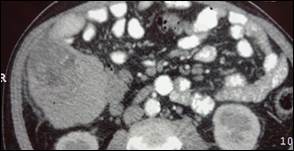

Se realizaron pruebas de imágenes como ecografía y tomografías donde se evidencia imagen nodular de 8 cm en el hígado derecho segmentos 6-7.

Figura 4: masa en hígado derecho segmento 6-7

Con los antecedentes y las imágenes se llegó al diagnóstico de HCC en Hígado Cirrótico por alcohol.

Figura 5: Masa Hepática Hepatocarcinoma

El diagnóstico de HCC se realiza mediante la realización de tomografía trifásica tiempo arterial tiempo portal y venoso tardío. Donde se pudo observar la captación del contraste en tiempo arterial y lavado rápido del contraste en fase portal.